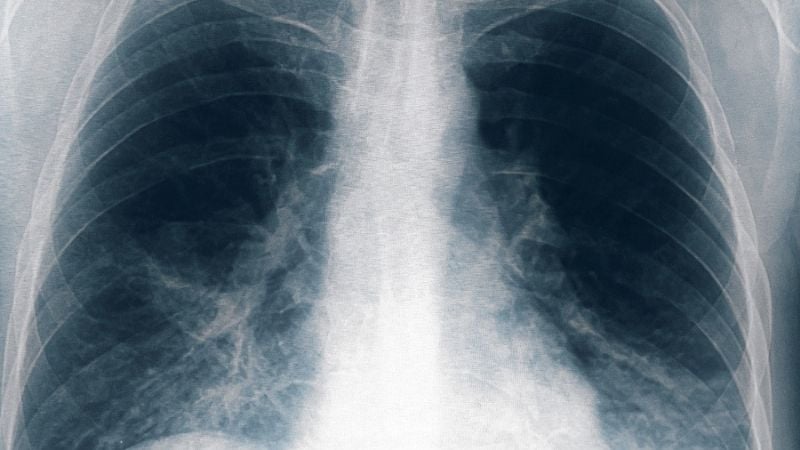

Ocho nuevos casos de neumonía bilateral en Tucumán

Otras ocho personas resultaron afectadas por el brote de neumonía bilateral causado por la bacteria legionella, una de ellas en estado grave, tras un cambio en el criterio de selección de los pacientes, con lo que suman 13 casos en total y seis fallecidos, informó el ministro de Salud de Tucumán, Luis Medina Ruiz.

"Estamos hablando de fiebre, de algún catarro respiratorio, o demás, de distinta gravedad, no necesariamente neumonía bilateral", detalló el titular de la cartera sanitaria tucumana.

"En general, esta enfermedad produce una mortalidad del 10 o 20% y es mucho mayor cuando se trata de neumonías", indicó el médico y añadió que "la mayoría de las personas que están graves o fallecieron son mayores, con comorbilidades severas."